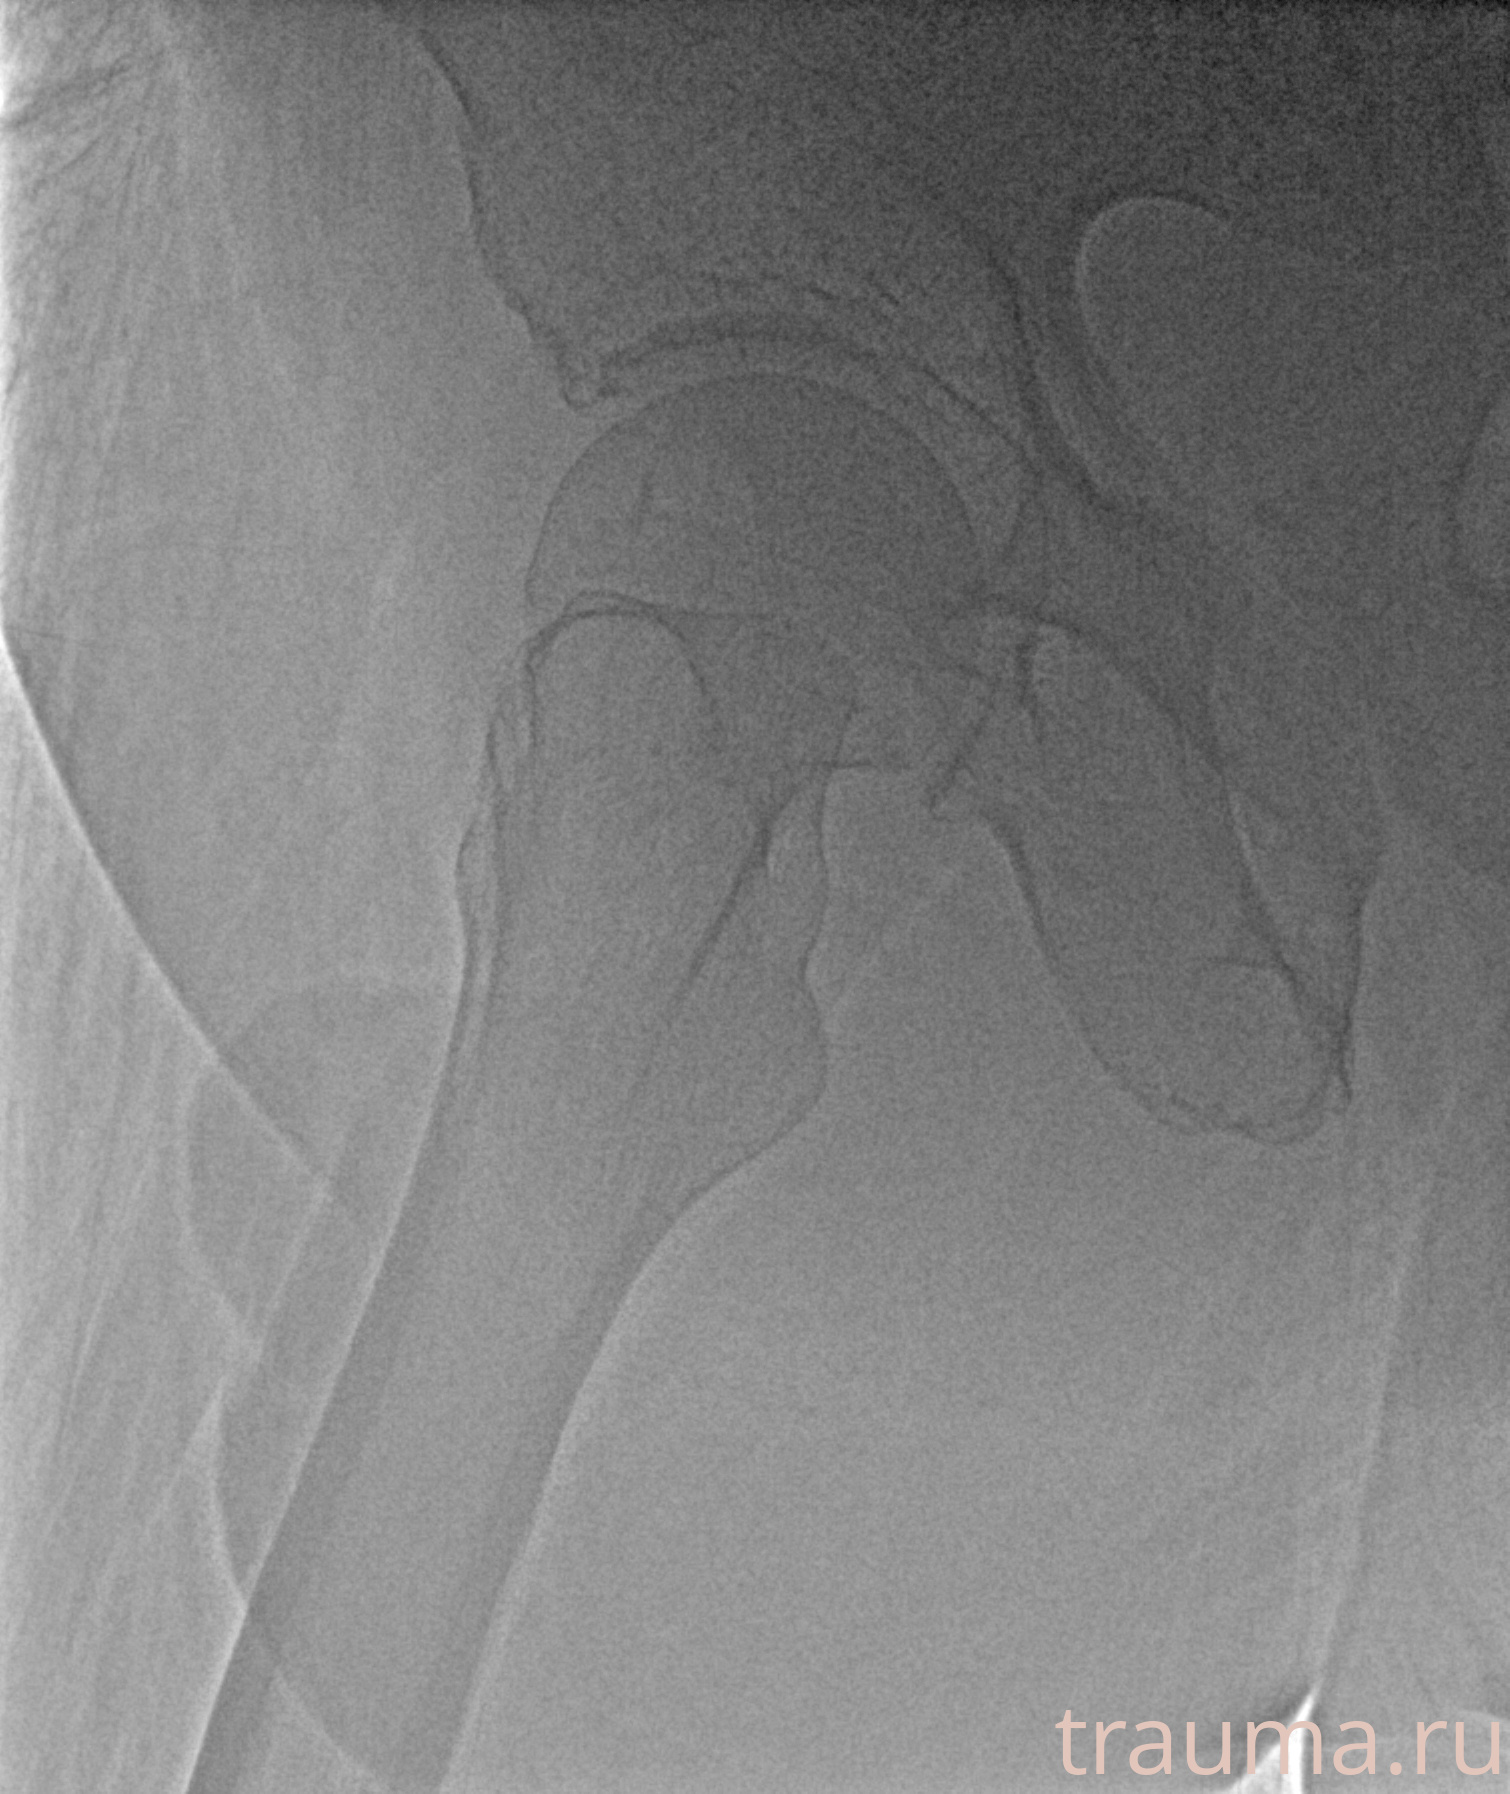

Рентгенограммы

Рентген на дому: по вашему адресу приезжает врач-рентгенолог, травматолог-ортопед с мобильным рентгеновским аппаратом, проводит диагностику травмы или заболевания, делает необходимые рентгенограммы, дает рекомендации по дальнейшему лечению. Получить качественные снимки в домашних условиях возможно благодаря уникальной методике, разработанной МосРентген Центром для института  Склифосовского